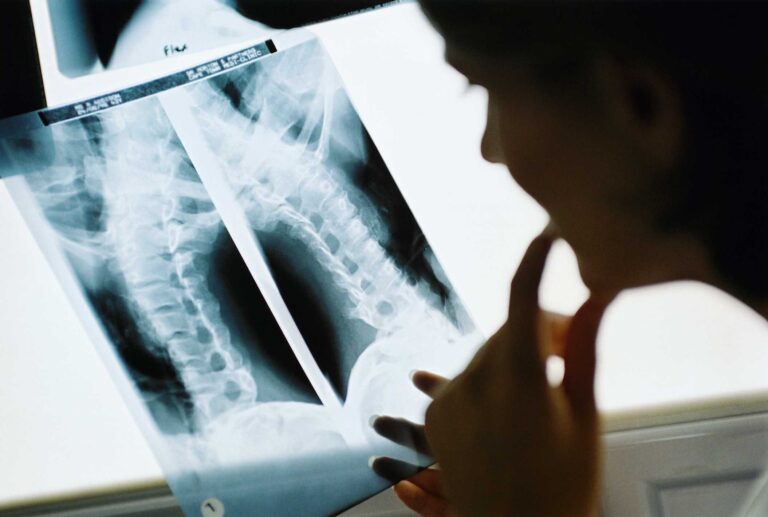

O que é o curso de técnico em Radiologia? Tire as suas dúvidas e saiba mais sobre a carreira!